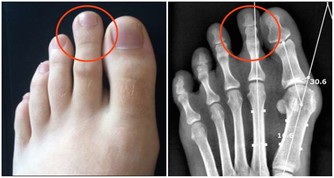

2去腳氣灰指甲常喝羅漢果可以緩解真菌引起的腳氣腳癢和灰指甲。對於反覆的腳氣可以用『齊峰堂足寶粉』泡腳,連續泡幾次就可以徹底殺菌,防止腳氣再次反覆。如果有灰指甲一直不好,可以用『齊峰堂灰甲清』抹抹,使用很方便,不用包甲,很快就好。因為是草本配方的,用好了可以防止再次出現。